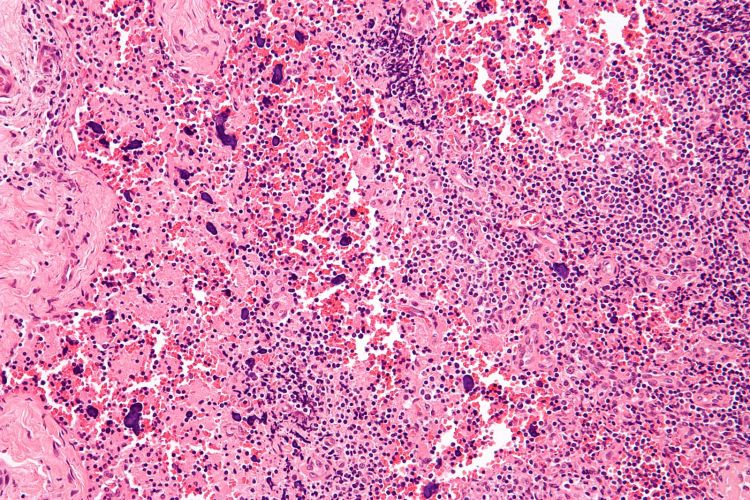

Lupus (systemic lupus erythematosus), a chronic autoimmune disease, often strikes young women of minority race and ethnicity. The onset of fatigue, joint pain, rashes and sometimes seizures, strokes or kidney failure can be devastating.

Photo caption: The image shows a high magnification micrograph of histomorphologic changes in a lymph node due to systemic lupus erythematosus. Public domain photo CC BY-SA 3.0 courtesy of Michael Bonert.